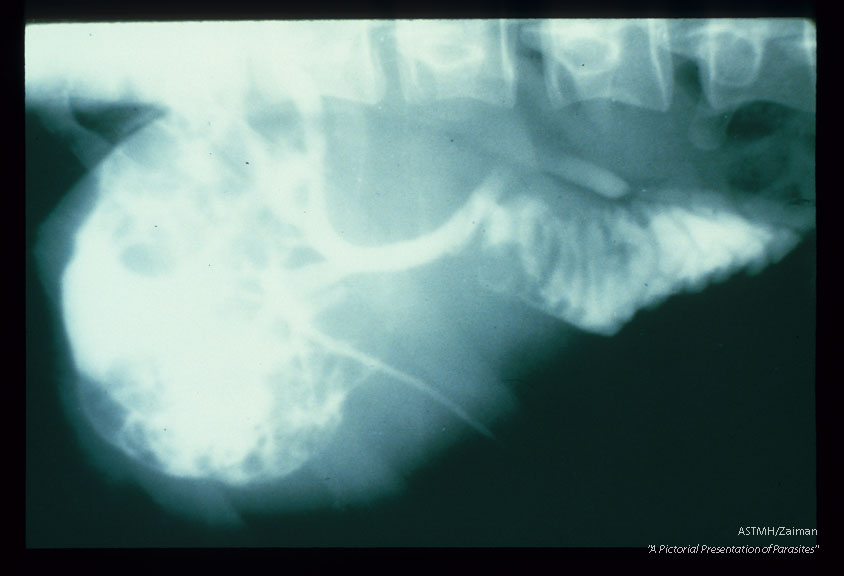

Contrast which appears white on x-ray was injected into the biliary tree of a patient who had a large cyst in the right lobe of the liver. The white contrast fills most of the cyst and the biliary tree proving a connection between the cyst and the bile ducts.

Echinococcus granulosus

Description: Contrast which appears white on x-ray was injected into the biliary tree of a patient who had a large cyst in the right lobe of the liver. The white contrast fills most of the cyst and the biliary tree proving a connection between the cyst and the bile ducts.